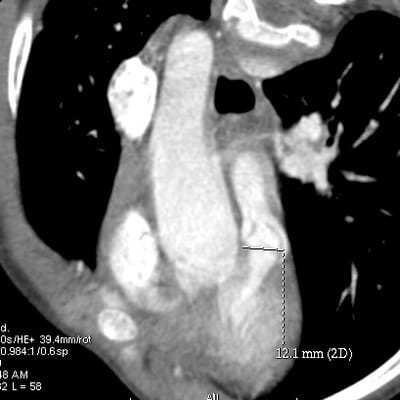

Les variations de forme d’une même cardiopathie pourraient constituer un séminaire entier. Nous avons isolé la coarctation de l’aorte pour raconter l’histoire de ses variants. Ceux-ci peuvent être importants ou être des variations morphologiques sans intérêt pour le patient ou son médecin. Certains détails peuvent avoir des conséquences diaboliques ou faire qu’une coarctation n’en est pas une.